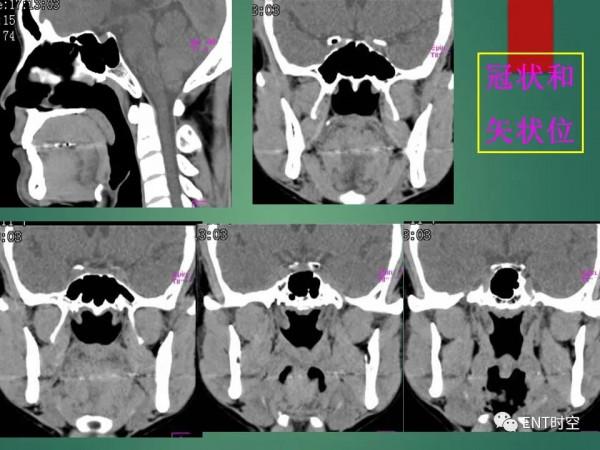

頭頸五官CT斷層解剖圖及常見病影像診斷

頭頸五官CT斷層解剖圖